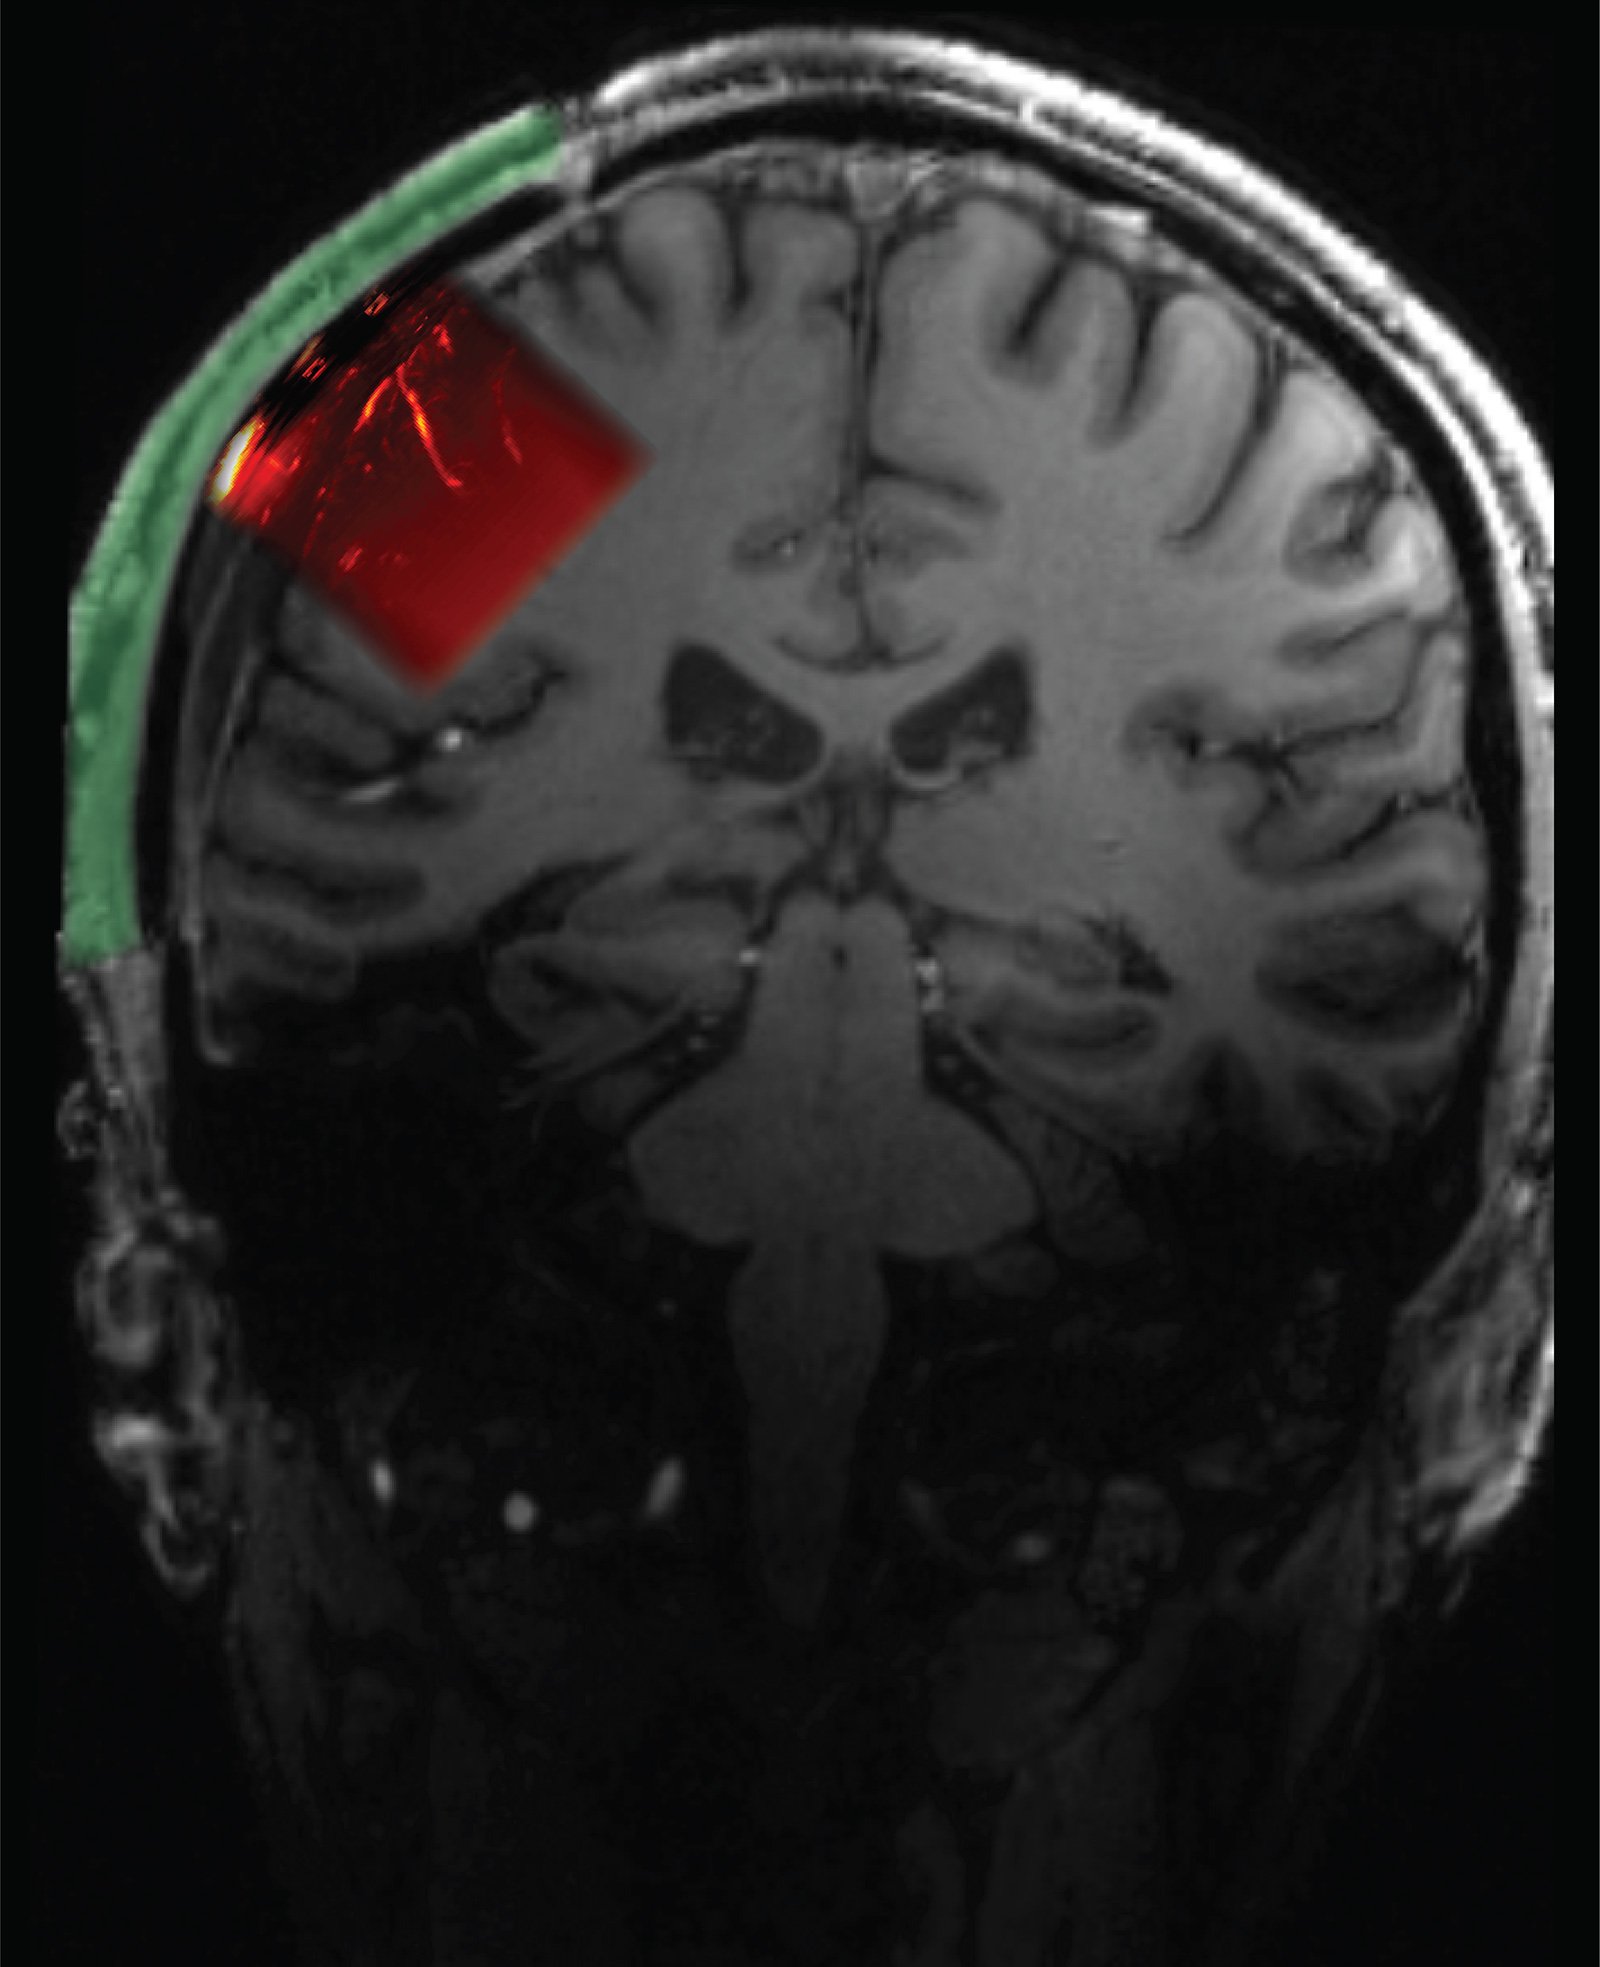

The resulting implant was 4 millimeters thick overall but had a 2 millimeter-thick window through which an ultrasound transducer could image a brain region known as the posterior parietal cortex and, behind it, the motor cortex. "This area of the brain, which is important for forming intentions and carrying out motor actions, has already been thoroughly studied via other methods in our lab," Andersen says. "With ultrasound, we can image the brain up to a resolution of one-fifth of a millimeter."

Schematic showing location of cranial prosthetic and area of brain that can be imaged through this prosthetic.